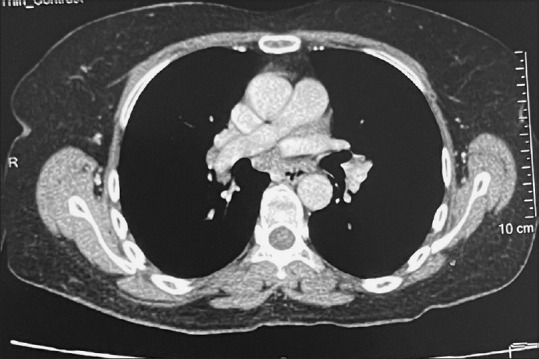

Morpheaform Sarcoidosis - A Very Rare Presentation of Sarcoidosis with a Brief Review of Literature.